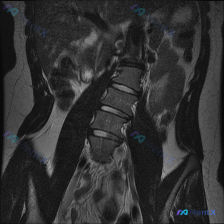

整理到一份有意思的腰椎影像读片资料,想和大家讨论下临床思维。 最初拿到这份资料时,提示观察脊柱侧弯,但仔细看MRI T2冠状位的客观描述: - 腰椎序列连续,生理轴线基本居中 - 下腰椎(L4-L5、L5-S1)椎间隙稍变窄,椎间盘T2信号略低 - 小关节信号欠均匀,椎旁软组织对称 - 骨髓信号均匀...

整理到一份有讨论点的影像资料,先跟大家同步核心信息: 1. 影像标注与初步印象的矛盾:这份资料最初被标注为 "Scoliosis(脊柱侧弯)",但看提供的单张腰椎MRI冠状位T2加权图像,描述里明确说「腰椎序列基本呈直线排列,未见明显的侧弯畸形」。 2. 图像里确实有的表现: - 椎体高度尚可,下腰...